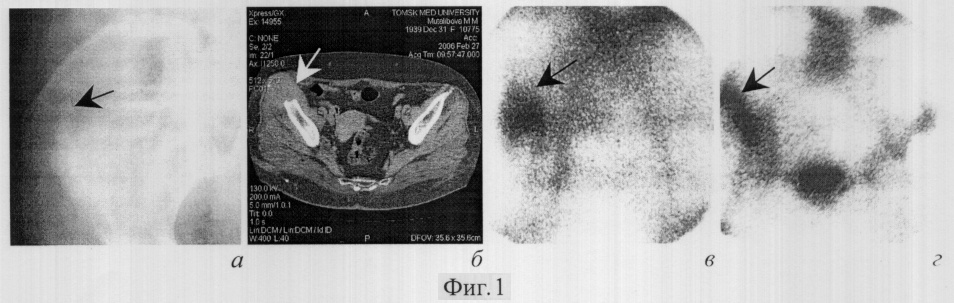

На рентгенограммах обеих стоп в прямой и косой проекциях (фигура 3а, б соответственно) №1846 от 16.06.05 определяются выраженные деструктивно-литические изменения, локализованные в области основной и ногтевой фаланг I пальцев с обеих сторон, средней и ногтевой фаланг II пальца справа. Резкое утолщение и уплотнение мягких тканей в области костно-деструктивных изменений. Диагностируется остеомиелит основной и ногтевой фаланг I пальцев с обеих сторон, ногтевой фаланги II пальца справа.

Дополнительно проведено исследование согласно предлагаемому способу – планарная сцинтиграфия обеих стоп с 199T1-хлоридом (16.06.05). Исследование выполняется в раннюю и отсроченную фазы (через 20 и 180 минут соответственно) после внутривенного введения 199T1-хлорида в диагностической дозе 5 mCi (185 MBq), с набором импульсов до 300000, в прямой и боковой проекциях. Осуществляется качественная оценка накопления РФП путем визуального выявления областей повышенного накопления маркера, оценки их наружных контуров и количественная – путем вычисления ER, DR180, RI180 (с обеих сторон). Для вычисления ER и DR180 в виду двустороннего симметричного поражения в качестве зон сравнения выбираются интактные области, прилежащие к очагам патологической гиперфиксации РФП (в прямой проекции – мягкие ткани латеральных отделов стоп, в боковой – мягкие ткани тыла стоп).

На сцинтиграммах, выполненных в раннюю фазу исследования в прямой и боковой проекциях (фигура 4а, в), в области дистальных отделов обеих стоп, преимущественно I и II пальцев справа и I пальца слева, определяются очаги аккумуляции 199T1-хлорида высокой интенсивности, с четкими наружными контурами; справа ER=2,85 в прямой проекции, ER=2,98 в боковой, слева ER=2,56 в прямой проекции, ER=2,76 в боковой. На сцинтиграммах, выполненных в отсроченную фазу исследования в прямой и боковой проекциях (фигура 2б, г), интенсивность аккумуляции РФП в данной области снижается до умеренной, контуры становятся менее четкими, «размываются»; справа DR180=1,94 в прямой проекции, DR180=2,04 в боковой, слева DR180=1,74 в прямой проекции, DR180=1,80 в боковой. Справа RI180=0,68 в прямой проекции, RI180=0,68 в боковой, слева RI180=0,68 в прямой проекции, RI180=0,65 в боковой.

Таким образом, и в прямой, и в боковой проекциях с обеих сторон RI180<1,0, a четкость контуров патологического очага гиперфиксации РФП в раннюю фазу исследования больше, чем в отсроченную. Следовательно, диагностируется неспецифический воспалительный процесс.

Результаты сцинтиграфии с подтверждены рентгенологически, а также совокупностью клинико-лабораторных данных, приведенных выше.